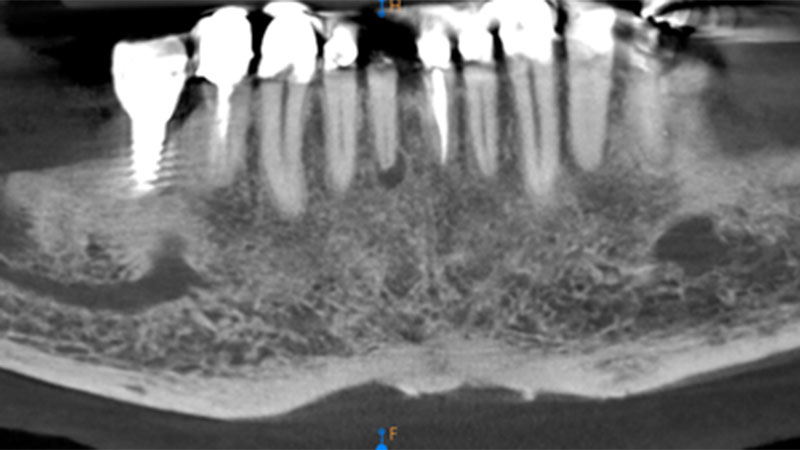

Silent progression: Full-arch implant peri-implantitis after 25 years without maintenance

Abstract Background: Peri-implantitis is a serious complication for both patients and clinicians. Affected implants typically show extensive bone loss in radiographs, are difficult to manage and usually lead to implant loss leaving significant alveolar bone defects. Methods: In 2009 the patient reported here received two endosseous implants to replace his mandibular left second bicuspid and first molar … Read more